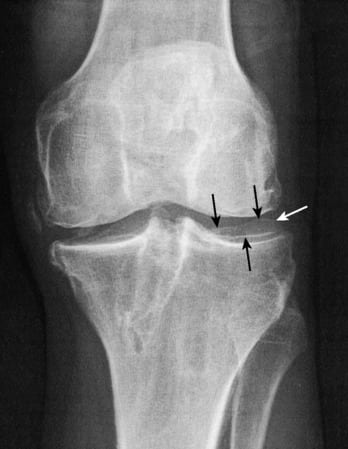

Вальгусная деформация коленных суставов — аномалия развития наследственного характера. При внешнем осмотре взрослого или ребенка ортопедом наблюдается Х-образное искривление ног. Одним из симптомов патологии становится боль в коленях, усиливающаяся после длительной ходьбы или подъема тяжестей. На рентгенографических снимках хорошо визуализировано нарушение процессов окостенения, а наружный мыщелок бедра выглядит скошенным.

Развитие внутренних бедренных мыщелков происходит несколько быстрее внешних, поэтому для бокового искривления ног характерно формирование открытых наружных углов между бедрами и голенями. Результатом становится расширение внутренней суставной щели, сужение наружной. Патологический процесс негативно отражается на состоянии связочно-сухожильного аппарата. Соединительнотканные структуры растягиваются; для стабилизации сочленения человек во время ходьбы вынужден широко расставлять ноги.

При нормальном состоянии здоровья центры головок бедренных костей и голеностопных суставов объединены биомеханическими осями, которые проходят через середину коленей. Возникающие нагрузки равномерно распределяются между обоими феморо-тибиальными отделами, границей между которыми являются мениски. Если механическая ось отклоняется наружу или внутрь, то происходит смещение силового вектора, увеличение нагрузки, как на латеральные, так и на медиальные мыщелки. Такое состояние называется синдромом гиперпрессии. Последствием избыточной нагрузки на определенные мыщелки является повышение уровня напряжения в костных, мышечных, хрящевых тканях, связках, сухожилиях. Из-за возникшего дисбаланса анатомические элементы сустава быстро изнашиваются, что становится причиной развития деформирующего артроза даже у совсем молодых людей.